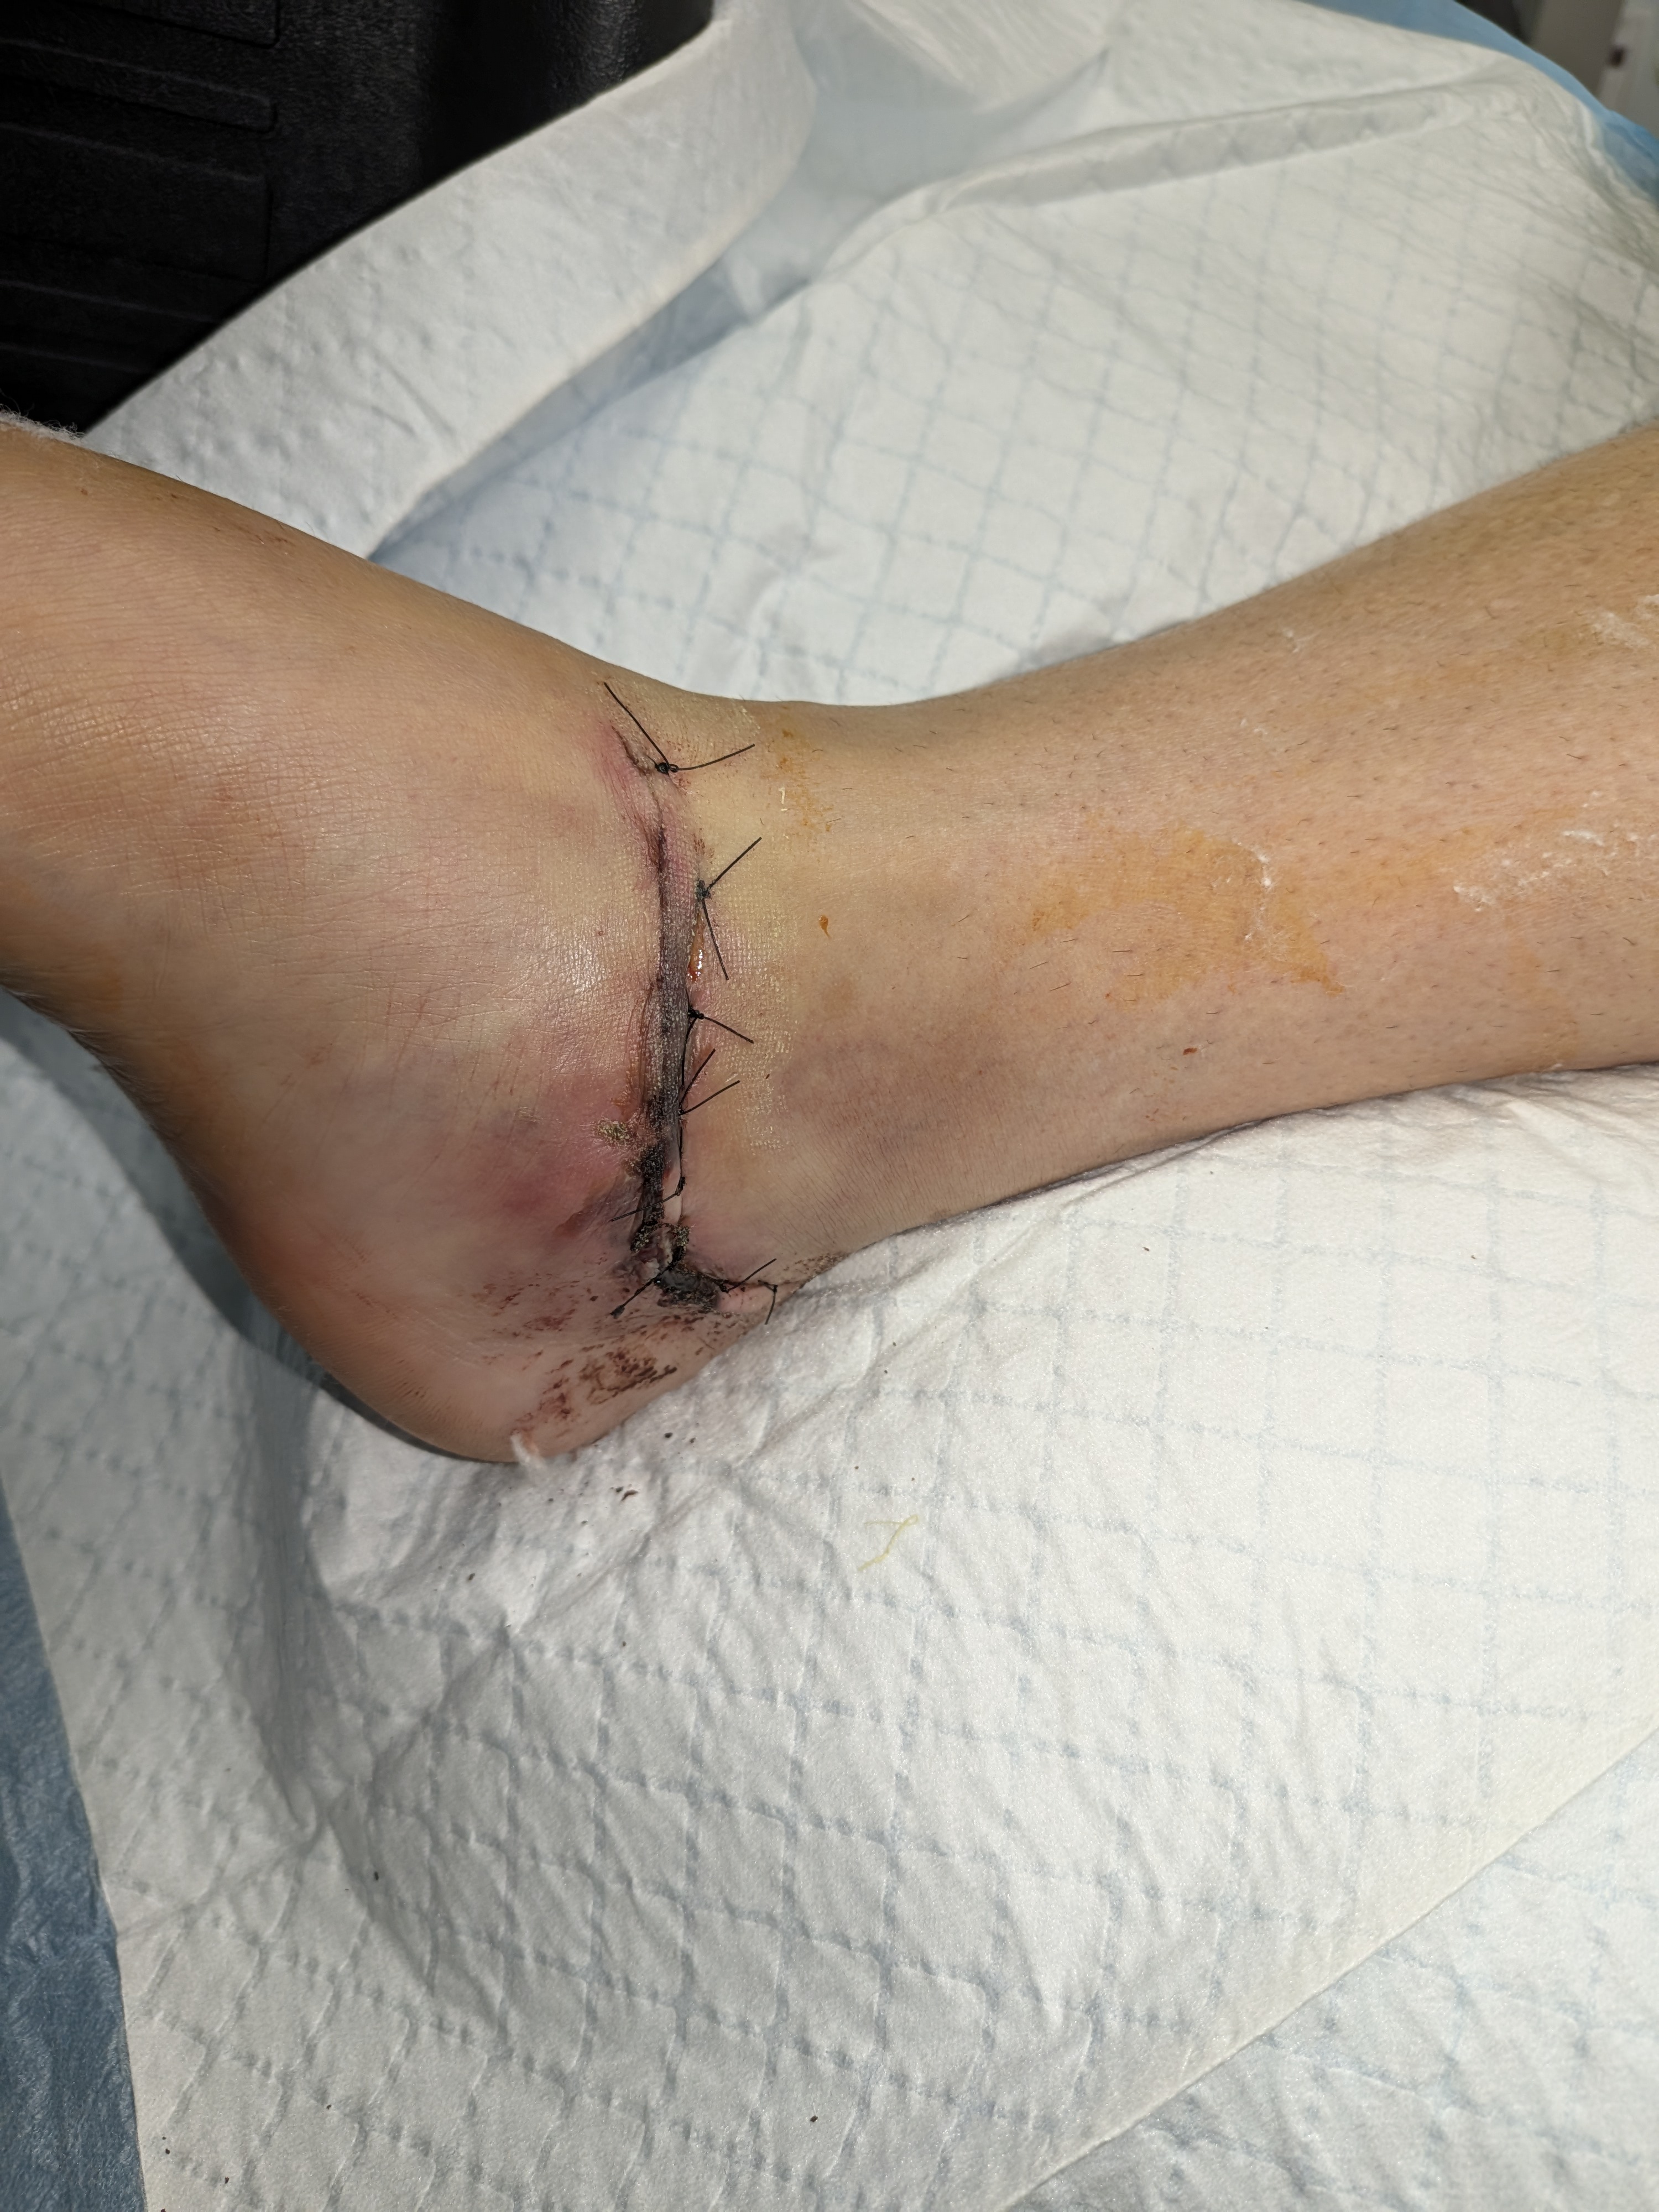

Hello, I am sure many of you have heard the news of Anita Featherstone (Morris) being involved in a head-on accident with a drunk driver. On Sunday afternoon, March 30th, she was leaving the Crosby/Houston area, heading to visit her daughter and grandsons. She was driving and missed her turn, and she was rerouted down a two-lane road she doesn't normally travel. As she was driving, she saw a car headed towards her in the other lane. She saw his tire slip off the road, and then everything went black. The next thing she remembers is waking up in the car (thinking she was dying). She was struggling to breathe and was in severe pain. With the help of a "good samaritan" that yielded, he was able to help her get out of the car and contact her family. She was not able to walk as part of her foot was missing with the bone exposed. Her sons (Michael & Matthew) arrived at the scene moments later and were informed by the responding officers that she was hit by a drunk driver and would need to be airlifted to Memorial Hermann Medical Center. She arrived at the hospital and was immediately rushed to trauma where they performed X-rays and CT scans to determine the extent of her injuries. She sustained major injury to her right foot and hand, with her right foot having a compound fracture with the heel crushed and her right hand also fractured. They were able to splint her hand but required emergency surgery on her right foot. She had many other contusions and bruises all over her body. She went into surgery several hours later where they cleaned out the wound, performed a nerve block, and set the foot. This is only step one in a very long road to recovery. She will need to have at least two more surgeries on her right foot. Her next surgery will not happen for at least two weeks because the swelling must go down. She is not able to put pressure on her right foot for two months. She will require physical and occupational therapy to learn how to walk again. Due to the nature of the injuries, she will not be able to use a walker, crutches, or a scooter for a couple of months. Unfortunately, the individual that hit her was driving an unregistered vehicle without insurance and has no license. He also was undocumented. Thankfully, they confirmed with blood tests that he was intoxicated, and Harris County will be bringing charges. Anita is self-employed and will not be able to work for months, and her medical bills are already piling up. Anything you can give would be much appreciated. Thank you all for hearing our story. God bless.